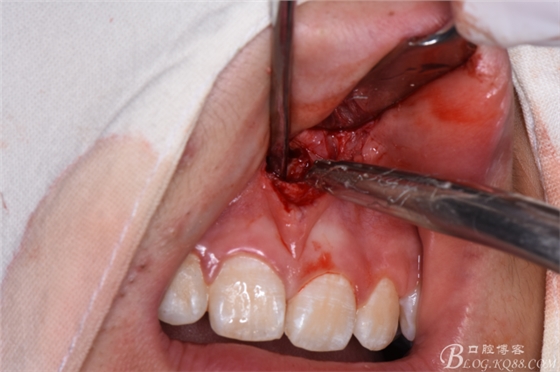

圖24.將多生牙分成牙冠和牙根兩部分,分別拔除。

圖25.拔除后??p合完成的雙切口。